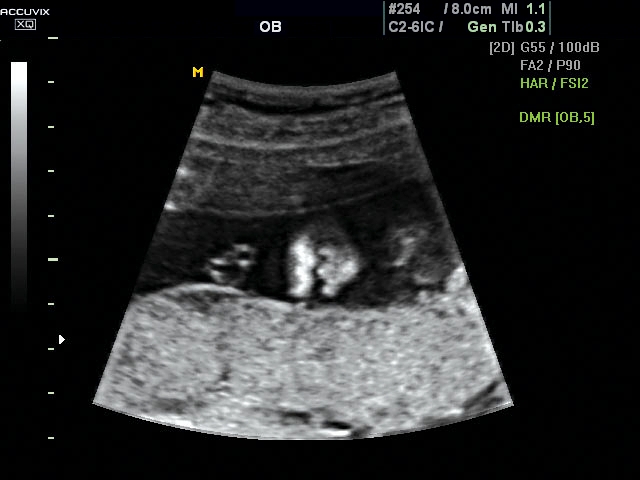

A pontos analízis és diagnózis iránti egyre növekvő igény kiszolgálására a MEDISON egy új real time képfeldolgozó technológiát fejlesztett ki Dynamic MR™ elnevezéssel. Az eljárás a diagnosztikus ismeretanyagot a precizitás és a pontosság egy teljesen új szintjére emeli. Használata az alapvető 2D ultrahang képinformáció real time, kivételesen kristálytiszta és kiemelkedően részletezett megjelenítését teszi lehetővé tűéles kontúrok és finoman rajzolt szövetstruktúra mellett. A DMR™ technológia ideális eszköze az ultrahang-diagnosztikának kezdve a szülészet-nőgyógyászattól a foetalis echon át az általános alkalmazásokig.

A DynamicMR alkalmazása az átlagos ultrahang teljesítményt a zaj és szemcsézettség jellegű műtermékek kiszűrése révén a vizuális diagnosztika, a precizitás és a pontosság új szférájába emeli. Figyelje meg a cerebellum, CSP és cisterna magna élstruktúráit, mennyire pontosan definiáltak és a teljes agyi struktúra ábrázolása a Dynamic MR alkalmazásával milyen látványosan javul.